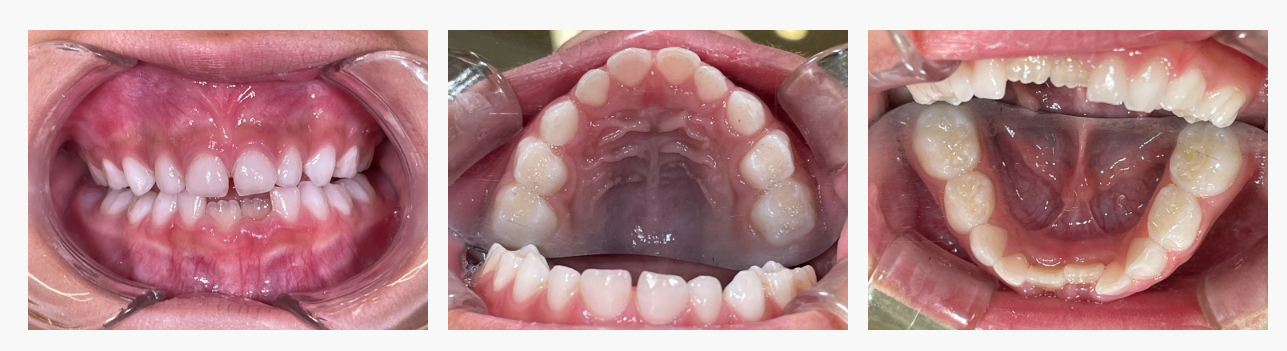

初診時の状態

・下顎左右1番に叢生(前歯のガタガタ)を認める

・上下顎ともに小さく、歯が並ぶスペースが不足

・乳歯列期ではあるが、将来的な叢生悪化が強く予測される状態

▼ Before(治療前)

▼ After(治療後)

■治療の結果

成長期の顎の発育を活かすことで、

・下顎前歯のガタガタが改善

・歯が並ぶスペースをしっかり確保

・将来的に歯並びが安定しやすい状態

をつくることができました。

歯を無理に動かさず、成長力を味方につけた小児矯正ならではの結果です。